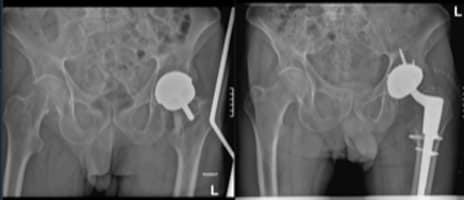

Post-traumatic osteoarthritis of the hip following fracture may result in severe pain and reduced mobility. Total hip replacement is an excellent...